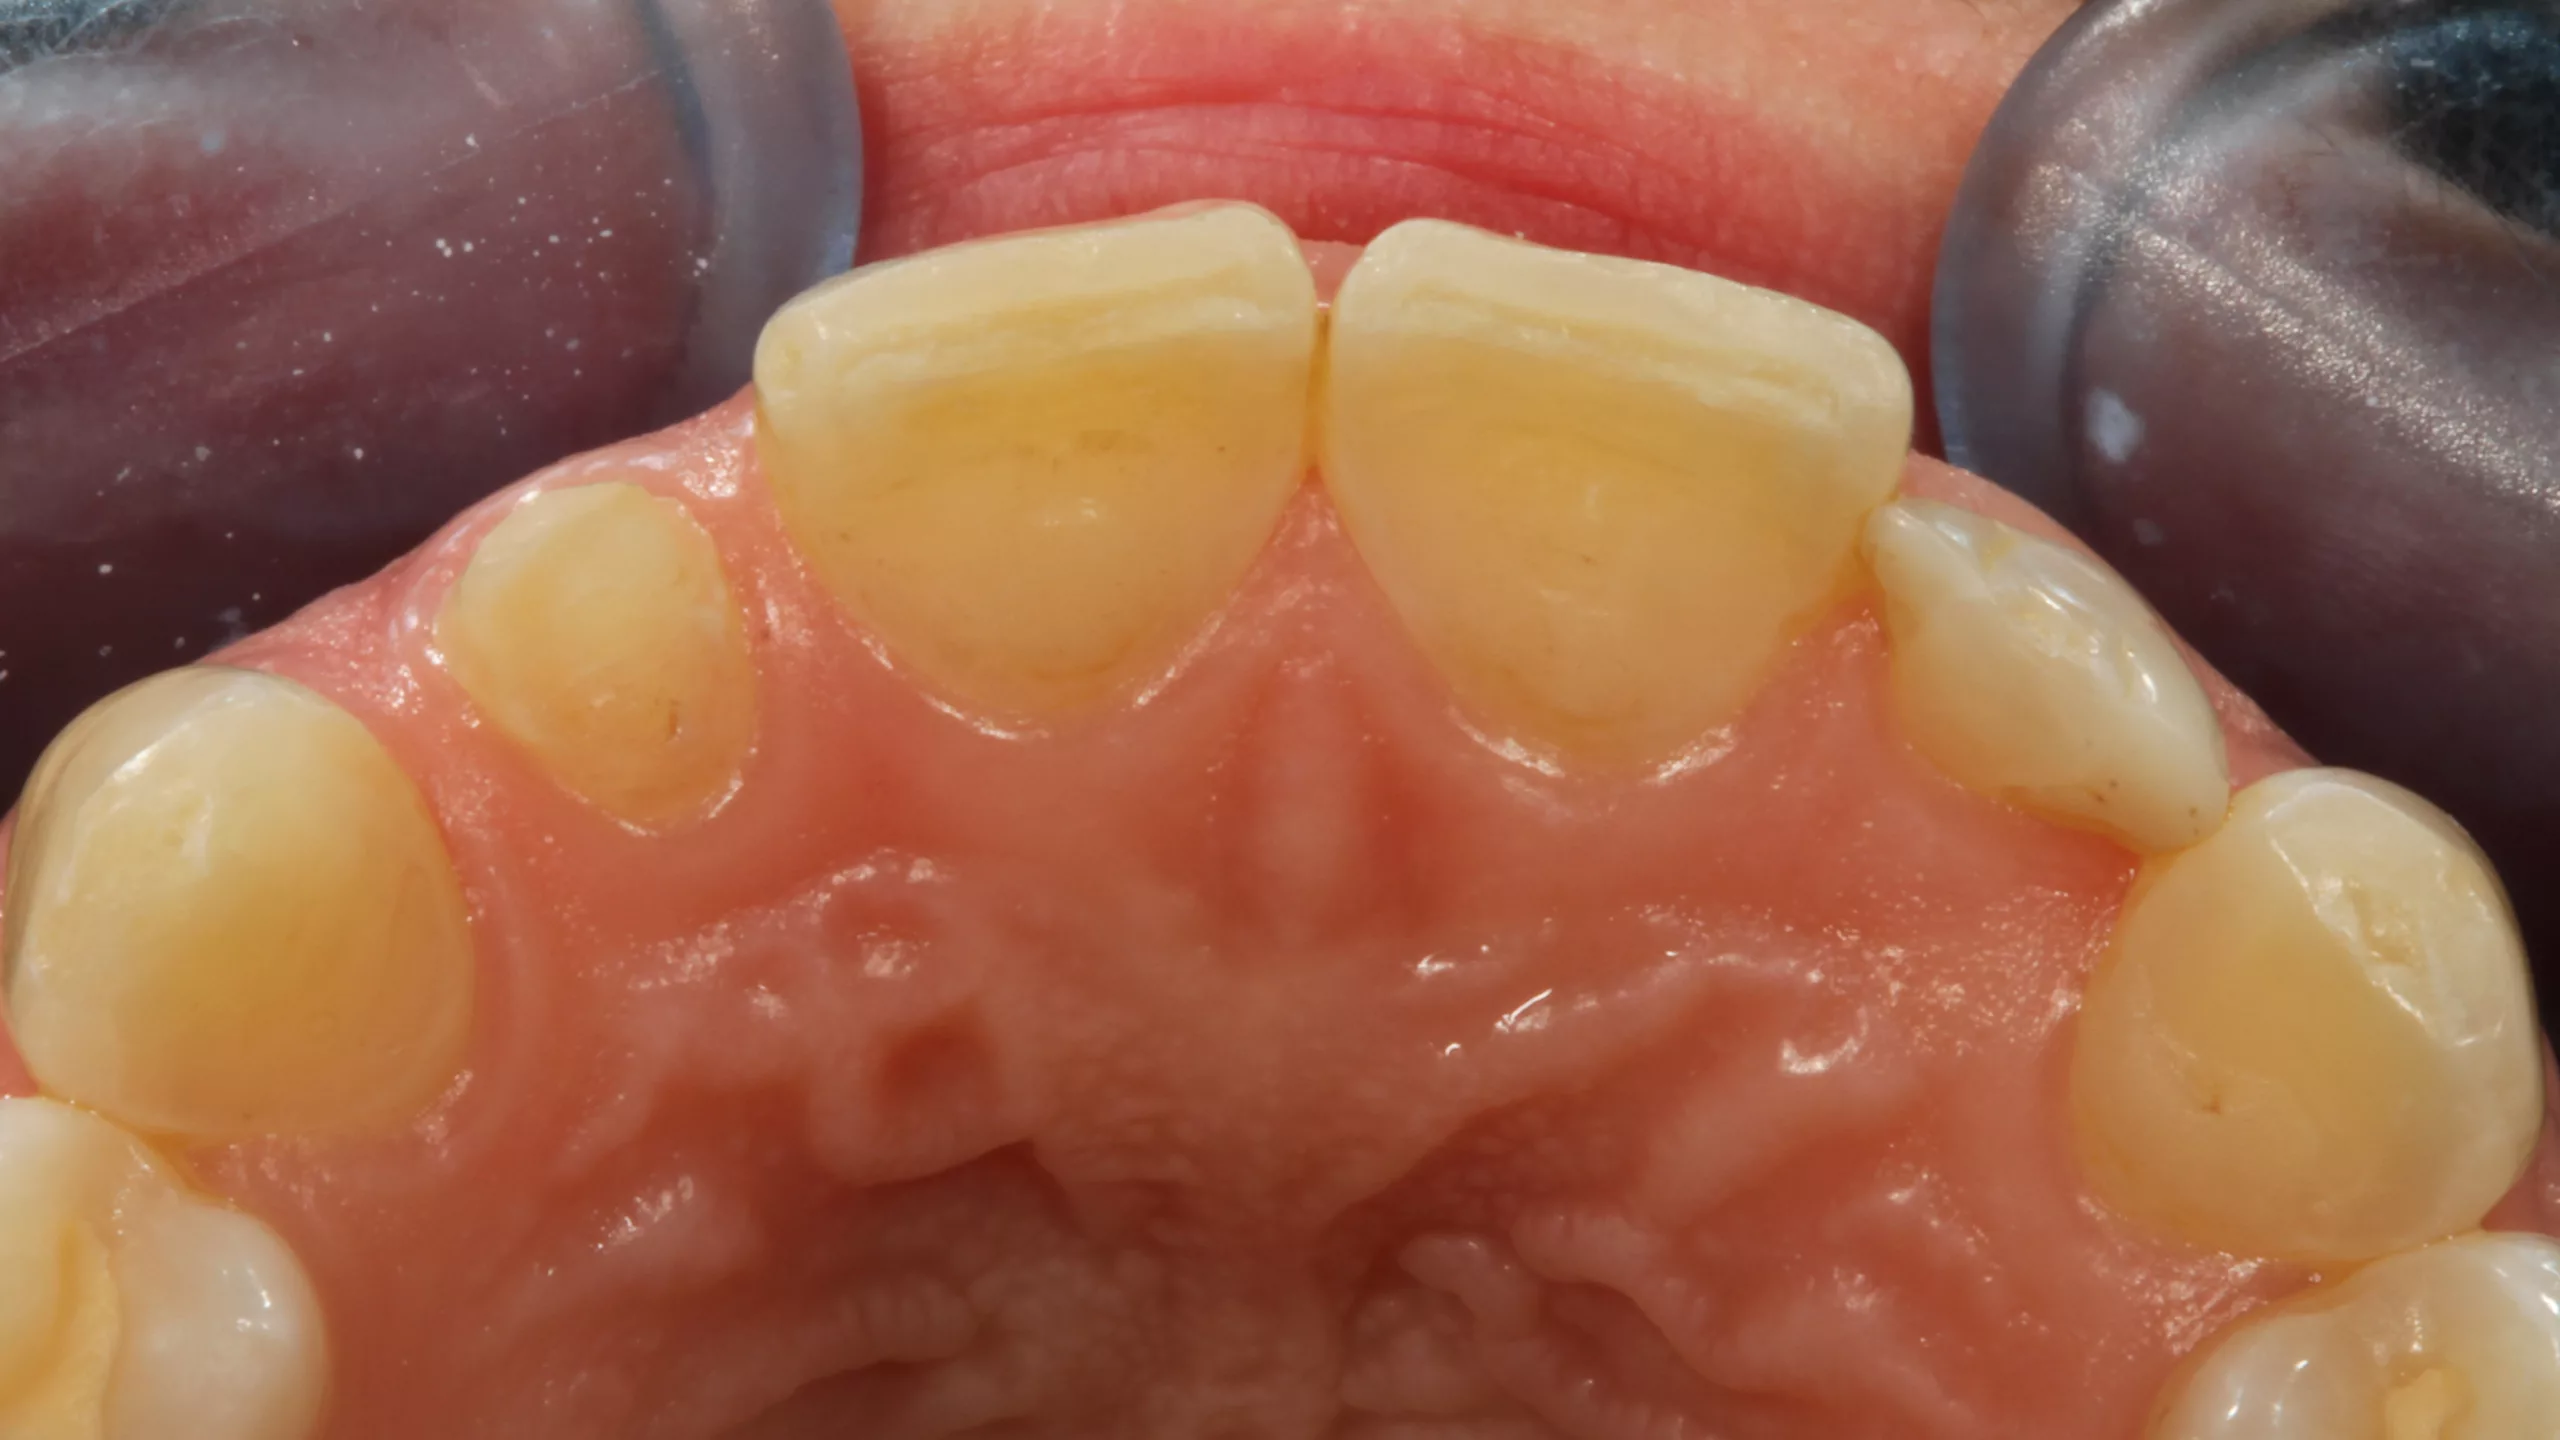

Die 32-jährige Patientin stellte sich mit einem komplett abgebrochenen, alio loco erstellten direkten Kompositaufbau an Zahn 22 vor (Abb. 10 und 11). Die beiden seitlichen Schneidezähne sind sehr kleine Zapfenzähne, deren ästhetische Verbreiterung vor einigen Jahren in direkter Technik vorgenommen worden war (Abb. 12). Aufgrund ihrer Press- und Knirschgewohnheiten mussten ihrer Angabe nach bereits mehrfach Ausbesserungsarbeiten vorgenommen werden. Die Vorpräparation ähnelte allerdings einer Veneerpräparation, sodass aufgrund der existierenden Vorpräparation und den erhöhten Anforderungen an die Stabilität im Beratungsgespräch eine indirekte Versorgungsform favorisiert wurde.

Direkte Frontzahnversorgungen mit Komposit funktionieren in der Regel hervorragend und sollten somit immer die 1. Wahl in der Überlegung alternativer Versorgungskonzepte darstellen. [6,31,37,55,58,59,62]. Es ist aber auch nicht zu unterschätzen, dass derartige Restaurationen sehr anspruchsvoll sein können [41,42]. Deswegen sind indirekte keramische Restaurationen – meist aus Glaskeramik – eine valide Alternative, wenn höchste ästhetische Ansprüche befriedigt werden müssen. [3,4,7,20,34, 40,43,44,57,65,89,98]. Ergibt allerdings eine Vorpräparation eine Ausgangssituation, die präparationstechnisch kaum verändert werden muss, und müssen erhöhte Anforderungen an die Bruchfestigkeit gestellt werden, ist eine indirekte Restauration die 1. Wahl, da keine weitere invasive Präparation erforderlich und eine bessere Langzeitprognose gegeben ist. So fiel die Entscheidung zugunsten einer labial verblendeten monolithischen Vollzirkonkrone (Abb. 13 und 14). Es wurde erwogen, Zahn 12, der mit einem vergleichbaren Kompositaufbau versorgt worden war, wie Zahn 22 mitzuversorgen. Da an dem Zahn 12 aber kein Akutereignis Berücksichtigung finden musste, verzichtete die Patientin auf diese zusätzliche Behandlungsoption. Bei der Formgestaltung wurde in Absprache mit der Patientin bewusst keine Rücksicht auf die jetzige Form von Zahn 12 genommen und eine symmetrische Versorgung bewusst ignoriert, um bei einer Neuversorgung von Zahn 12 in der Zukunft dann keine Formkompromisse eingehen zu müssen. Die Form der neugestalten seitlichen Schneidezahnkrone orientierte sich somit ausschließlich an den Zähnen 21 und 23 und den gegebenen vertikalen Dimensionen.